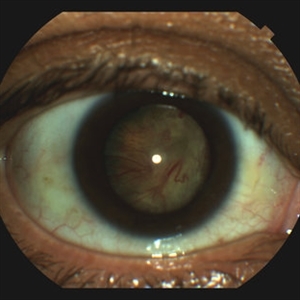

Globe Perforation With Retinal Detachment

Patient presenting with globe perforation with a penetration seen at below the inferior arcade with some scattered hemorrhage and a retinal detachment.

Photographer: Rakesh Juneja

Condition/keywords: globe perforation